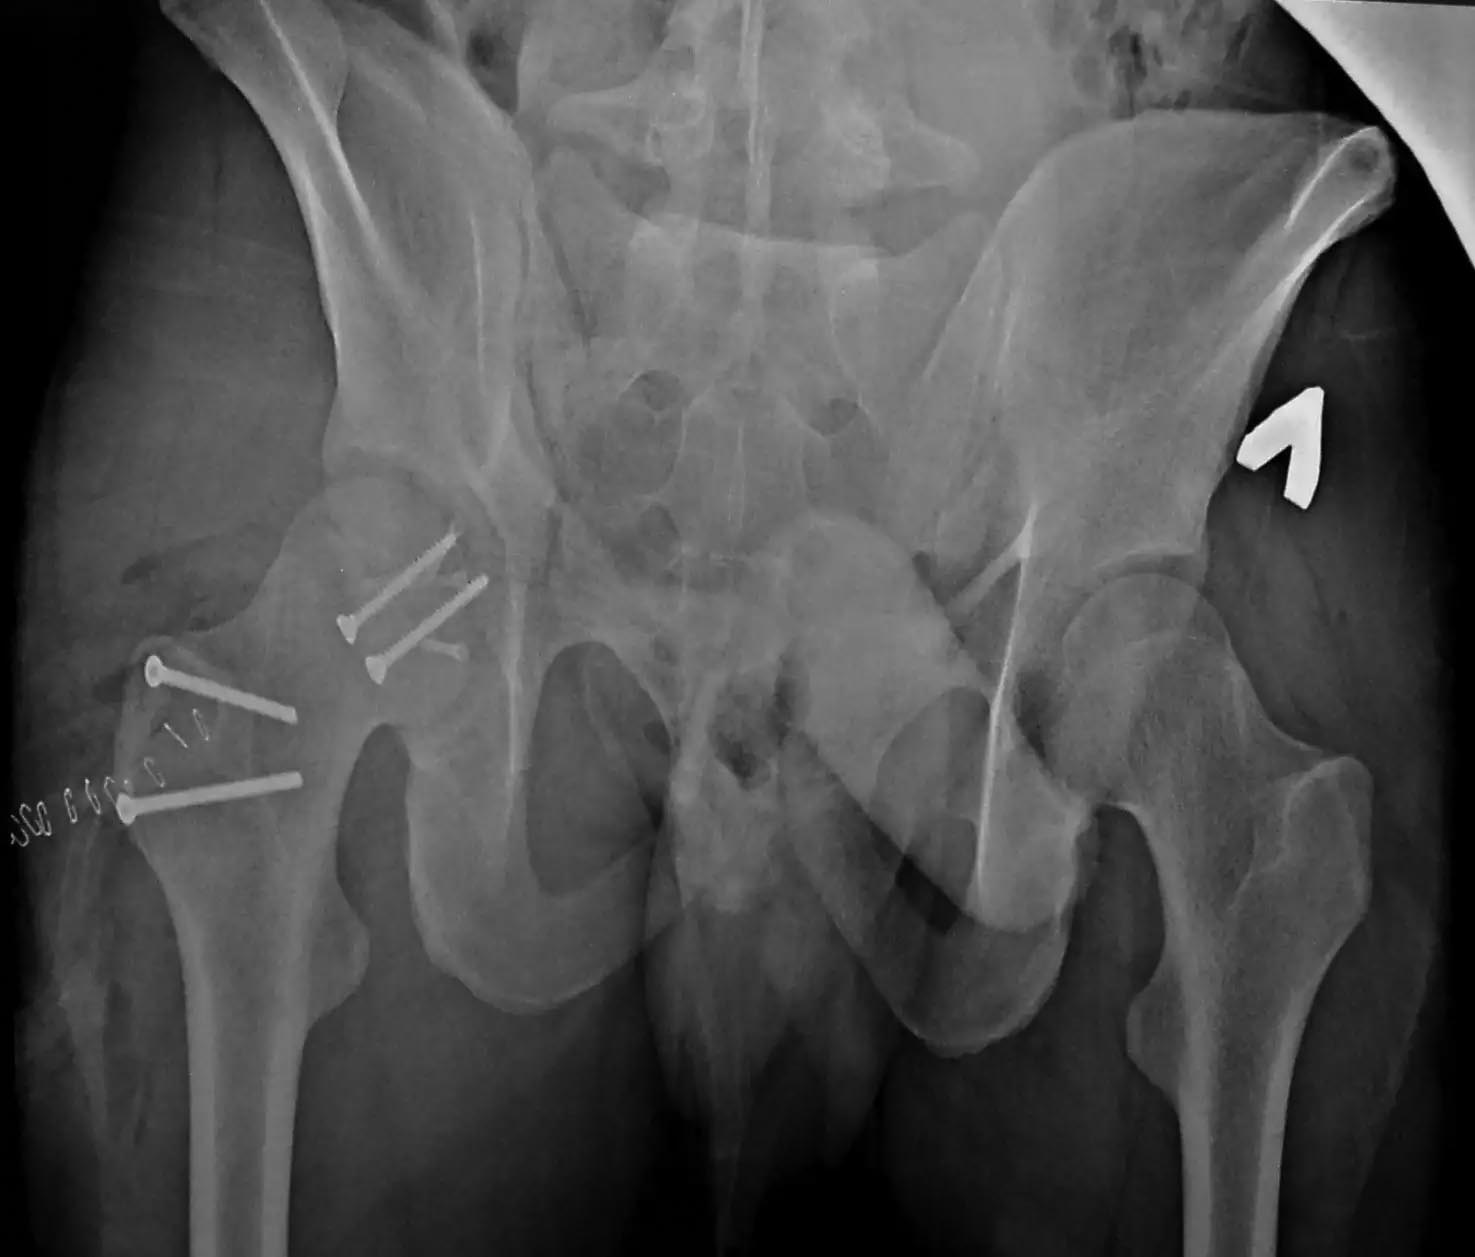

Молодой человек 20 лет ДТП 23.02.2015, Диагноз: Сочетанная травма.

Закрытый переломо-вывих головки и перелом заднего края вертлужной

впадины (Pipkin4) правой бедренной кости. Открытый подтаранный вывих

правой стопы. При поступлении в ЦРБ вправление вывиха головки бедра и

подтаранного вывиха стопы. Далее перевод к нам в Травмоцентр и

03.03.2015. через 8 дней операция, выполнен остеосинтез головки 3-мя

самокомпрессирующими винтами Autofix под разными углами с погружением в

субхондральный слой. Доступ Kocher-Langenbeck с флип-остеотомией

большого вертела и задним хирургическим вывихом головки бедра. В полости

сустава два свободно-лежачих фрагмента хряща головки, которые были

удалены. На снимках виден дефект хряща головки после репозиции.

Небольшой фрагмент заднего края фиксирован двумя спонгиозными винтами.